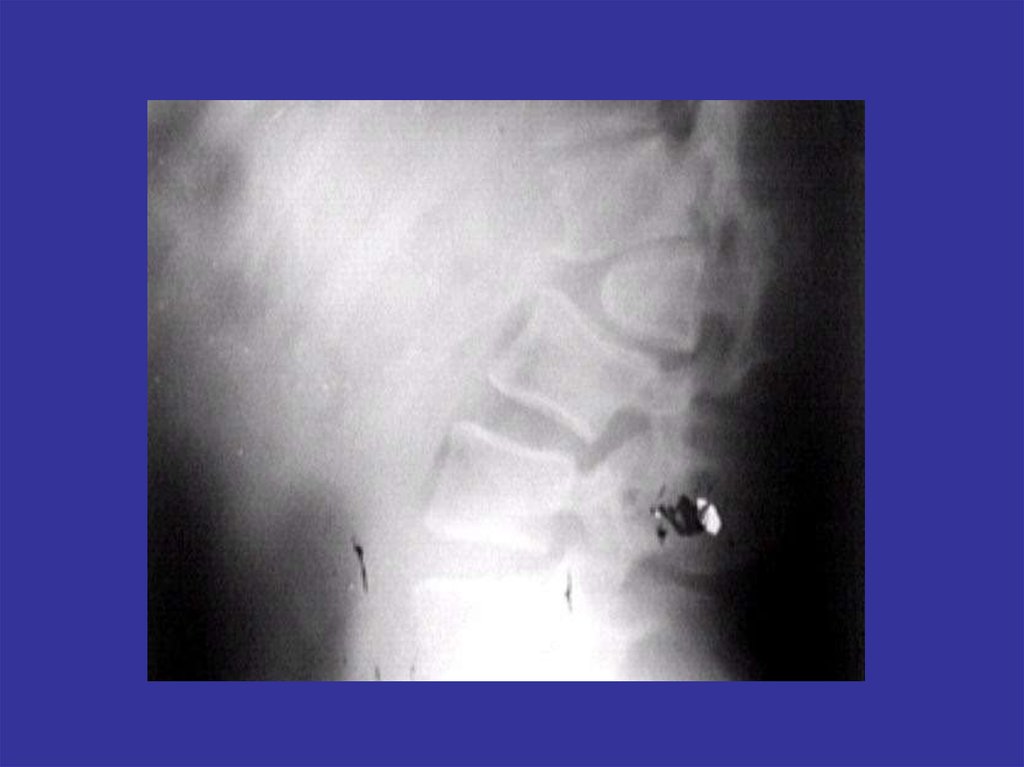

Аномалии развития позвоночника